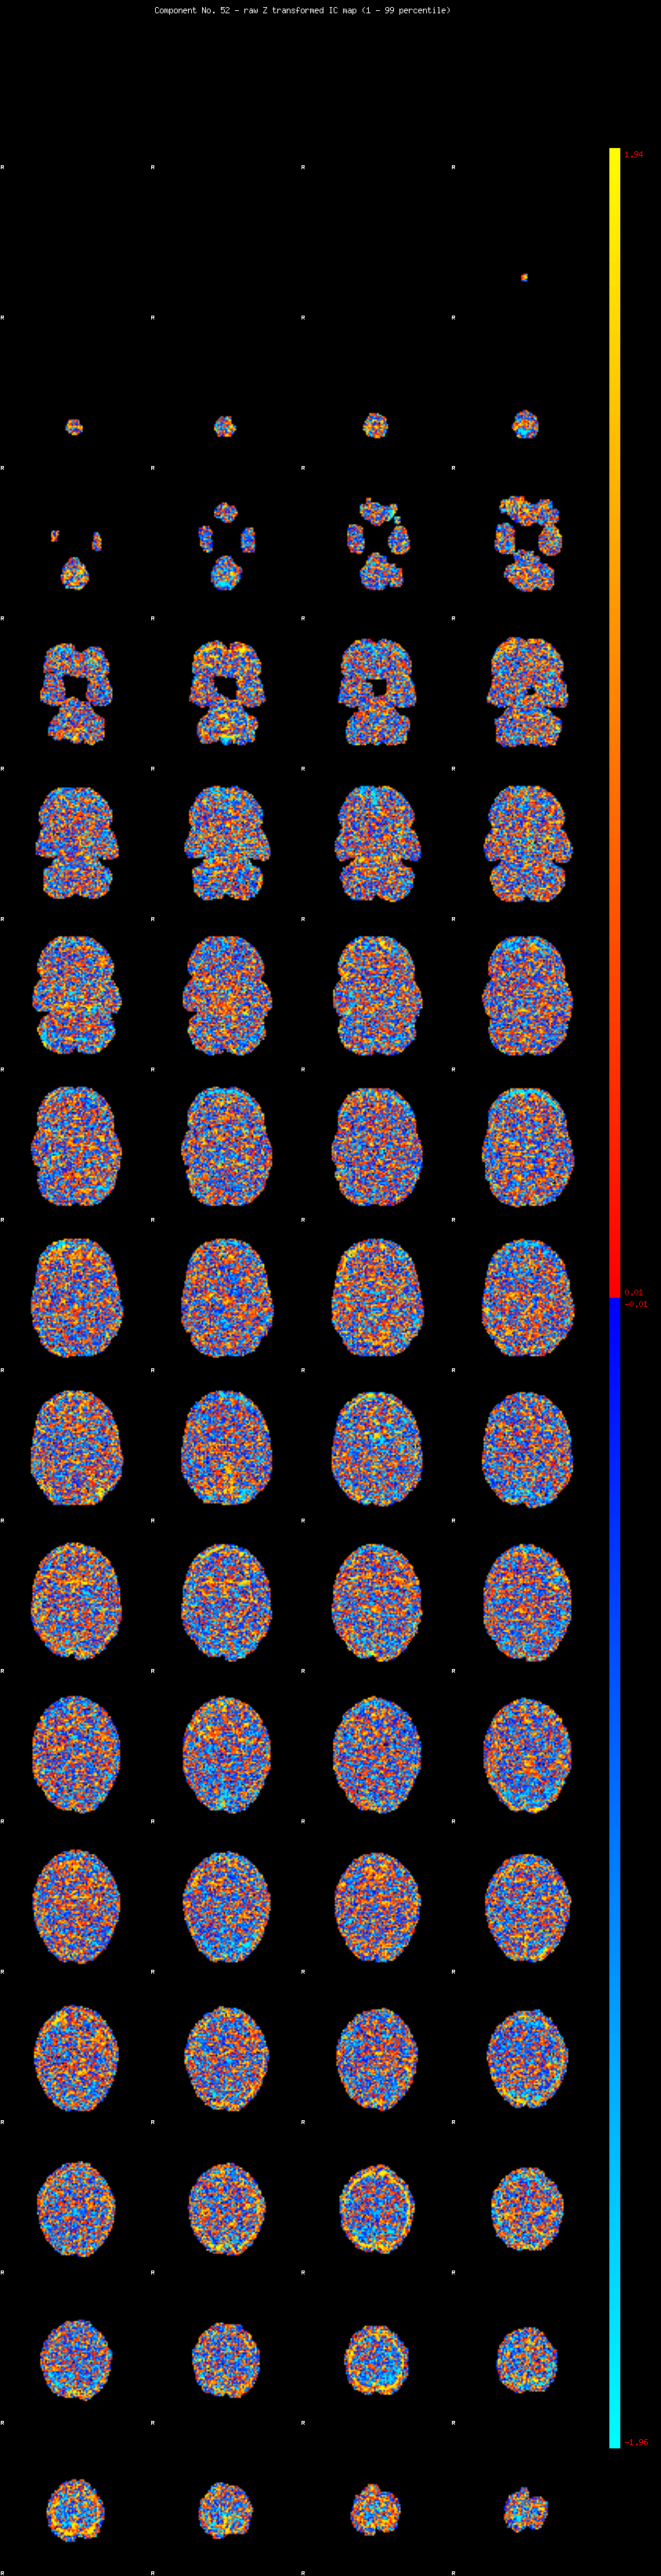

IC_52 Mixture Model fit

Means : 0.000000 1.988712 -1.997895

Vars : 1.000000 0.620459 0.637299

Prop. : 0.922235 0.037232 0.040532